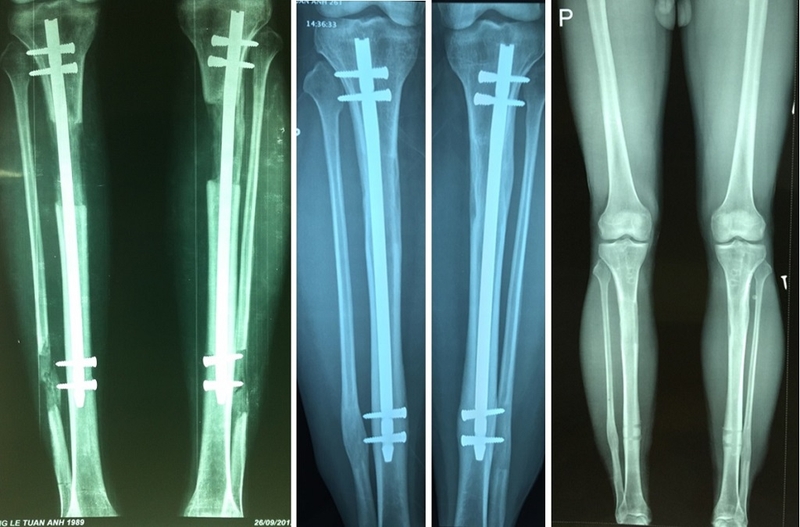

Phẫu thuật kéo chân tăng chiều cao là một loại phẫu thuật chỉnh hình phục hình cơ bản có mục tiêu là gia tăng chiều cao của người bệnh. Phương pháp này thường được thực hiện bằng cách cắt xương chân tại một hoặc vài vị trí rồi sử dụng thiết bị đặc biệt để kéo dãn xương đó ra thêm một khoảng nhất định. Sau đó, xương sẽ tự động phục hồi và lấp đầy khoảng trống được tạo ra, nhờ đó làm tăng chiều cao của người bệnh.

Quá trình phẫu thuật kéo dãn chiều cao yêu cầu sự can thiệp của một bác sĩ phẫu thuật chuyên nghiệp và diễn ra dưới sự theo dõi của đội ngũ y tế có kinh nghiệm. Thời gian phục hồi và kết quả của phẫu thuật này có thể thay đổi tùy thuộc vào nhiều yếu tố, bao gồm phương pháp phẫu thuật cụ thể, tuổi của người bệnh, tình trạng sức khỏe chung và việc tuân thủ của người bệnh đối với chỉ định sau phẫu thuật.

Quy trình phẫu thuật tăng chiều cao mới nhất là một quy trình phức tạp và yêu cầu sự chuyên nghiệp của các bác sĩ phẫu thuật chuyên về lĩnh vực này. Dưới đây là các bước thực hiện chính: